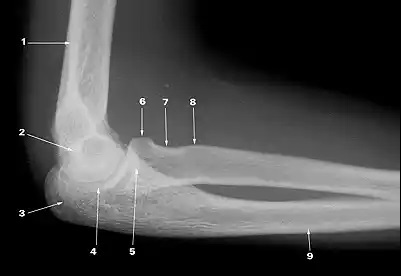

What does 1 indicate?

supracondylar ridge

What does 2 indicate?

medial supracondylar ridge

What does 3 indicate?

olecranon fossa

What does 6 indicate?

capitulum

What does 7 indicate?

olecranon

What does 8 indicate?

trochlea

What does 9 indicate?

coronoid process of ulna

What does 4 indicate?

medial epicondyle

What does 5 indicate?

lateral epicondyle

What does 10 indicate?

proximal radioulnar joint